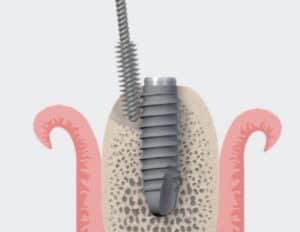

Mechanical disinfection remains the cornerstone of the management of Peri-implantitis. But do we best achieve our goals? From simply rinsing with saline and rubbing with a gauze to a whole Er:Yag Lazer, there is a whole spectrum of techniques and devices that seem to achieve comparable results. How do we choose and where do we strike the best balance?

As there seems to be no “one size fits all”, today we review the most common devices for mechanical disinfection of implants, under the light of clinical applicability. So let’s take a purely clinical standpoint today and discuss some clinical “tips and tricks” to help you make the most of each approach!